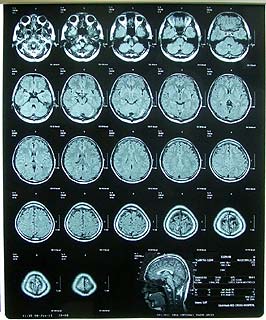

えーっと、どうも低髄液圧症候群ということがわかりました。

確かに髄液が漏れているのをMRIの写真で確認させてもらいました。

いつからなっていたのかが謎です。

思い当たるとすれば2月11日のスキーで激しくコケたときでしょうか。3月11日のスキーでもコケたかも。

それくらいしかないよなぁ。あとは整骨院で首をコキっとやったとき?そんなんでなるのかね?

まぁ、とにかく漏れているのは確かなのでなんとかせねばなりません。

以前CTのときネタに写真を撮れば良かったと後悔したのですが、ぐりこちゃん情報によるとお金を払えば写真を売ってくれると聞いたので尋ねてみると…

「デジカメ持っていたら撮っていいですよ」

と言われたので

「こんなこともあろうかと用意してますた(゚∀゚)」

とポケットからFinePix Z2を取り出す漏れ(ぉ

もう遠慮なくハァハァしながら一枚一枚撮影してきますたよ。

かなりご満悦でございます(*´д`)(ぉ